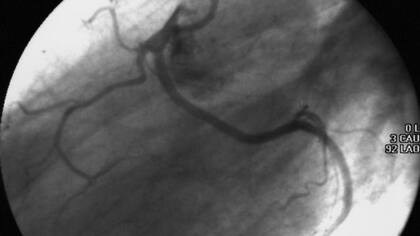

Esta tarde se conoció la noticia del procedimiento quirúrgico en el corazón al que fue sometida hoy la diputada nacional Elisa Carrió. Se trató de una angioplastia por una lesión severa de la arteria circunfleja, por lo que fue necesario la colocación de dos stents.

“En la parte izquierda del corazón, hay dos arterias: la Descendete Anterior y la Circunfleja, que fue la afectada en la paciente Carrió”, explicó a LA NACION el doctor Oscar Mendiz, jefe del servicio de Hemodinamia de la Fundación Favaloro.

Los profesionales que atendieron a Carrió decidieron debía ser operada luego de realizarle un estudio angiográfico de las arterias coronarias, lo que permitió finalmente detectar la dolencia mencionada.

“Con un equipo especializado de rayos X y la introducción de líquido de contraste se observa la arteria tapada y se determinan los pasos a seguir para solucionar el problema: toma de medicación, una angioplastia, o una cirugía de bypass, que es un procedimiento más complejo”, afirmó Mendiz.